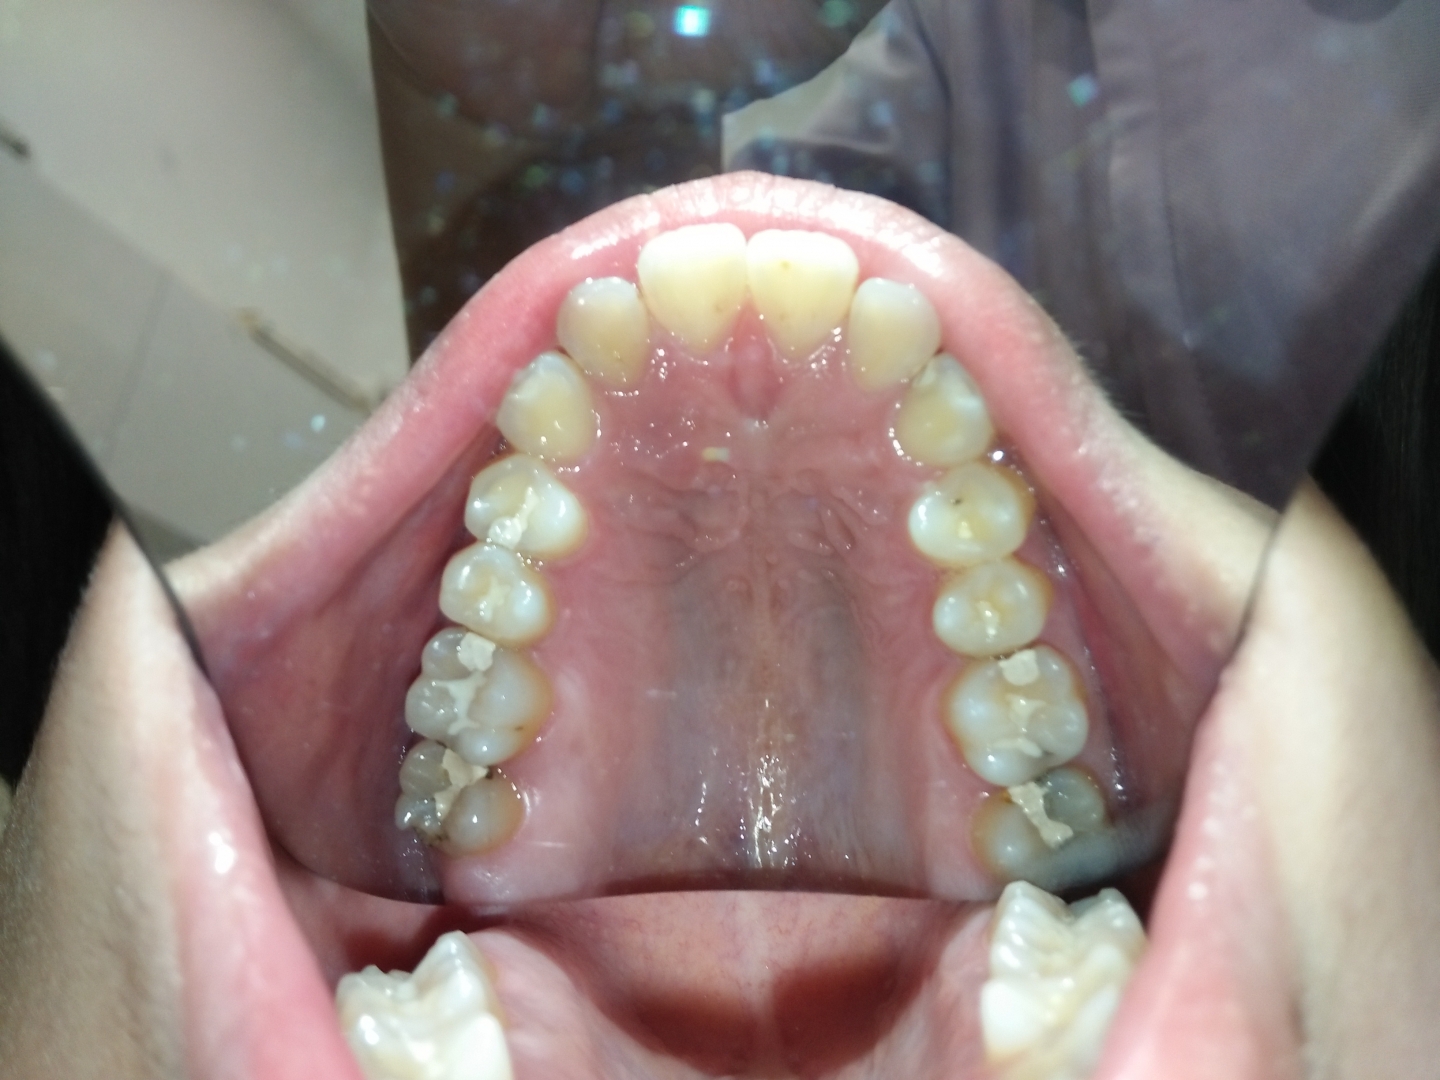

患者年約19歲,於門診中表示要檢查蛀牙,醫師已於之前檢查時告知家長,患者因咬合不正,造成牙縫易塞,容易造成蛀牙及將來

為牙周病的病灶; 家長表示孩子要準備考試,待考試完畢再決定是否做治療??

因此醫師囑咐一定要使用牙線,及沖牙機, 加強牙縫及牙齦周圍的清潔。

時隔不到半年回診,原先蛀牙旳牙齒下方竟然又二度蛀牙了,且患者強調有使用牙線及沖牙機,但這樣情況的牙齒

却不只一顆而已。重複塞東西,重複蛀牙,醫師只能和家長強調:咬合的重要性,因咬合力量不正產生的咬合傷害

會很嚴重, 孩子的牙齒禁不起一蛀再蛀,最糟可能會傷害到牙髓神經。

且口內這樣一直反覆蛀牙的牙齒,為數不少,對牙齒健康非常不利。

因為只是一味的

填補蛀牙而不考慮蛀牙形成原因